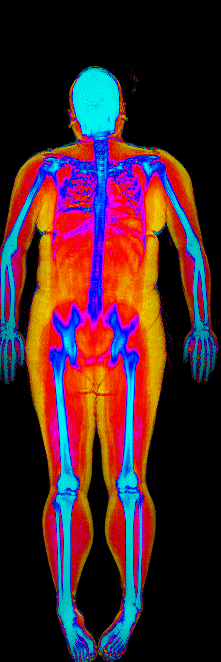

What Fat Loss Looks Like on a DEXA Scan

Lost 30.2 lb of fat, gained 3.9 lb lean · 240 → 214 lb · Age 43

Lost 27.9 lb of fat · 225 → 191 lb · Age 40

Lost 23.7 lb of fat · 186 → 155 lb · Age 34